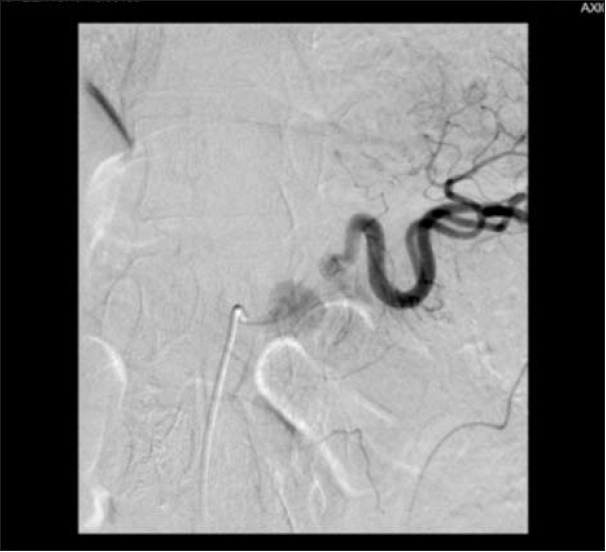

However, the 6th p.o. day marked a sudden re-onset of melenic stools, cold sweats and pallor. As the patient was hemodynamically stable he was immediately transported to the Radiology Department and another celiac trunk

angiography was performed, revealing rupture of the splenic artery near its emergence from celiac trunk. Unfortunately, no further angiographic therapeutic measures were performed as the patient developed a hemodynamic instability, with the procedure being promptly

aborted, and the patient requiring immediate transfer in the operating room for an emergency re-laparotomy. Access to the WON was managed difficultly because of dense adhesions, initially through the lesser omentum, and finally

through the gastro-colic ligament to obtain better exposure, with difficult local dissection because of fibrosis. A major source of bleeding from splenic artery close to its origin was identified, which required cross clamping of the aorta at the level of the hiatal hiatus to reduce the flow and allow good identification of the artery and its lesion. The breach was sutured with polypropylene 5/0. The spleen did not show any sign of ischemia and it was left in place. The postoperative course was uneventful, with no further bleeding, and patient was discharged in the 14th p.o. day. The 3 months and one-year post-operative follow-up showed normal healing.